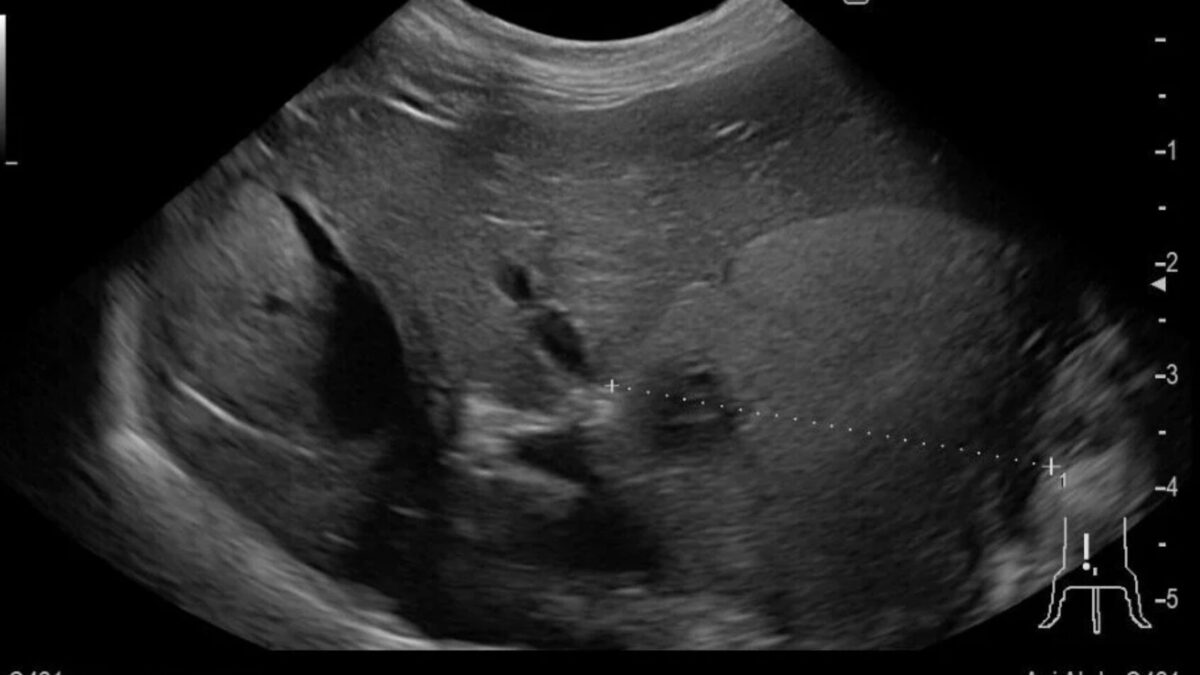

超音波で確認すると肝臓の基部に腫瘍が認められました。犬の肝臓腫瘍は肝細胞癌の可能性が高いので、摘出を行いました。